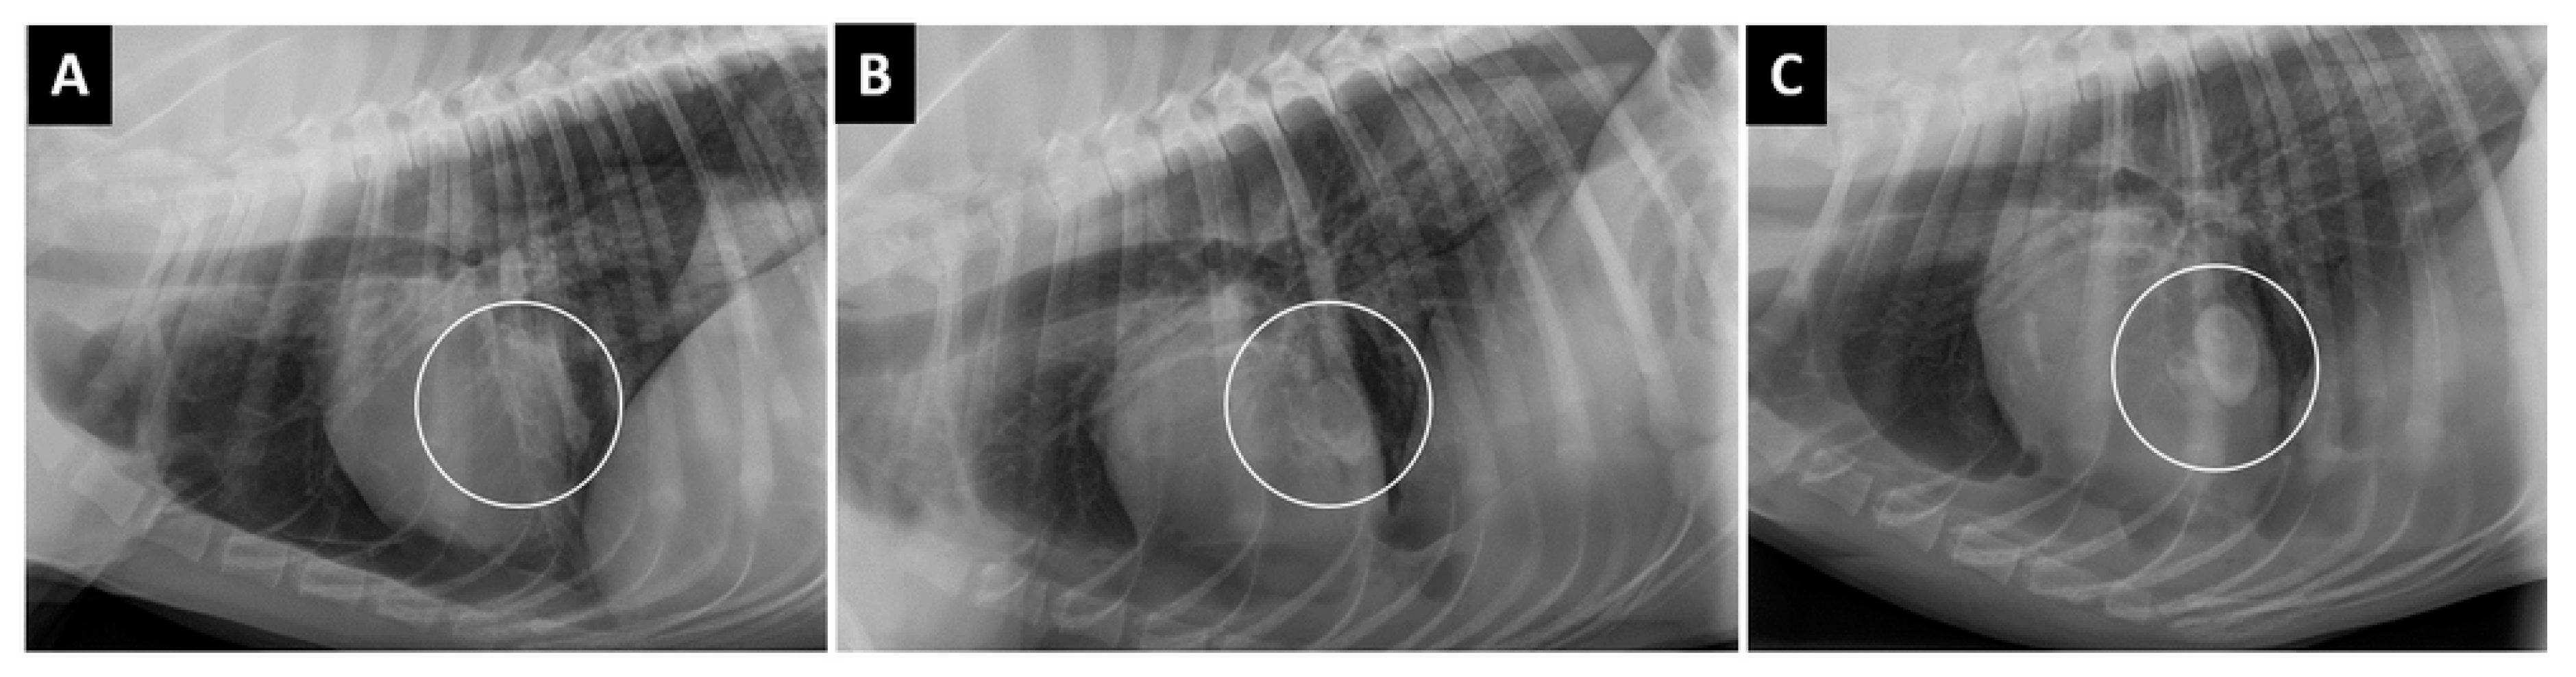

Figure 9.

(A–C) Right lateral projections of a traumatized dog showing changes over time of lung lacerations. (A) On admission, an alveolar pattern was noted in the middle lobe area (circle) surrounded by a diffuse interstitial pattern. (B) Two days later, in the same area (circle) a large ovoid lesion with hydroaeric level was noted (pneumohematocele). (C) Four days after admission, in the same area (circle) the lesion was clearly visible (hematocele); another small lesion, with air–fluid levels, was noted.